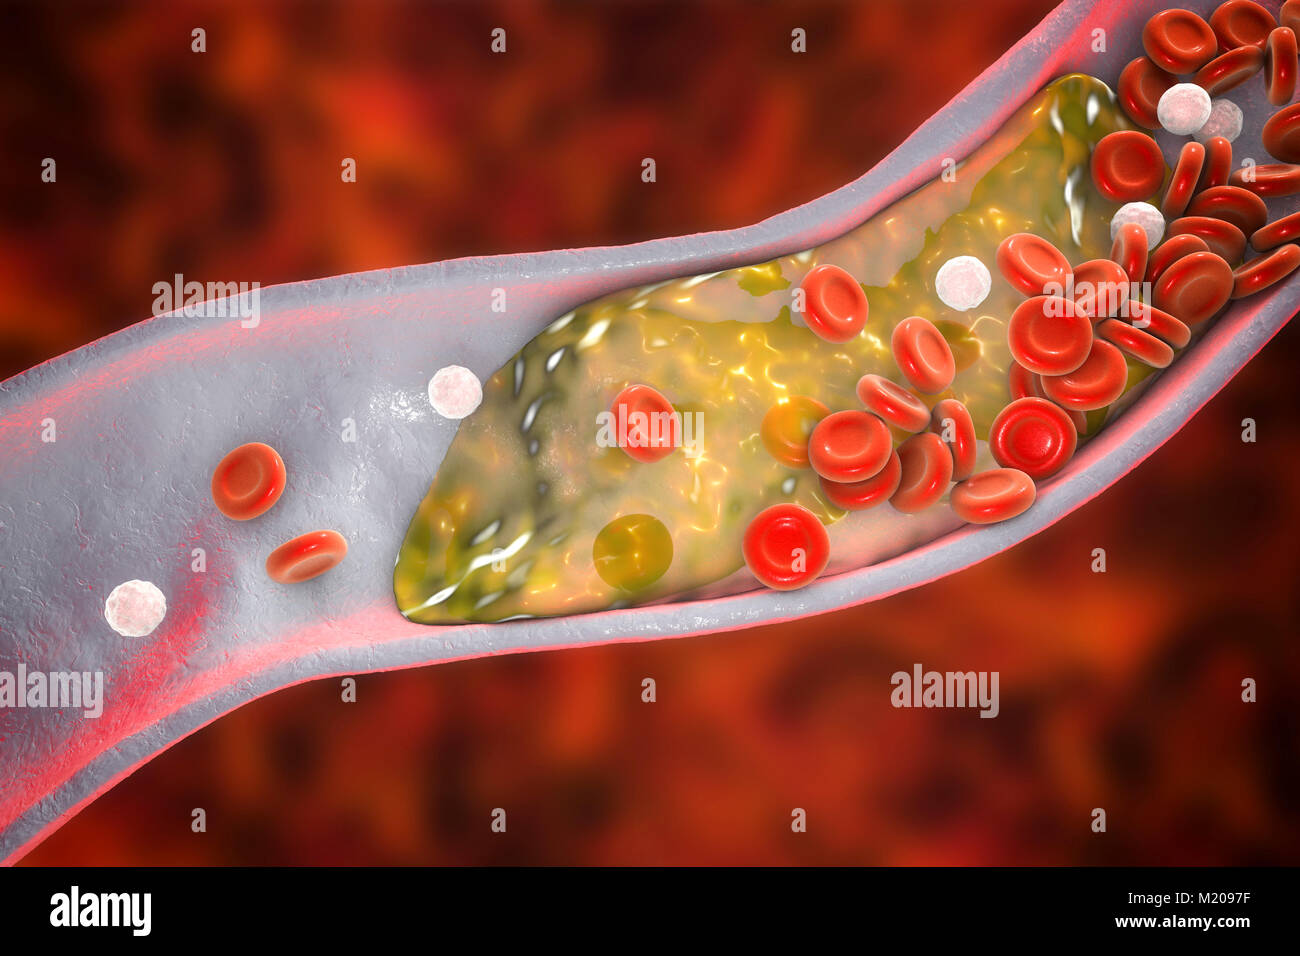

Atheromatous plaque inside blood vessel, computer illustration. A cholesterol atheroma is causing a narrowing of an artery (atherosclerosis). Stock Photohttps://www.alamy.com/image-license-details/?v=1https://www.alamy.com/stock-photo-atheromatous-plaque-inside-blood-vessel-computer-illustration-a-cholesterol-173340259.html

Atheromatous plaque inside blood vessel, computer illustration. A cholesterol atheroma is causing a narrowing of an artery (atherosclerosis). Stock Photohttps://www.alamy.com/image-license-details/?v=1https://www.alamy.com/stock-photo-atheromatous-plaque-inside-blood-vessel-computer-illustration-a-cholesterol-173340259.htmlRFM2097F–Atheromatous plaque inside blood vessel, computer illustration. A cholesterol atheroma is causing a narrowing of an artery (atherosclerosis).